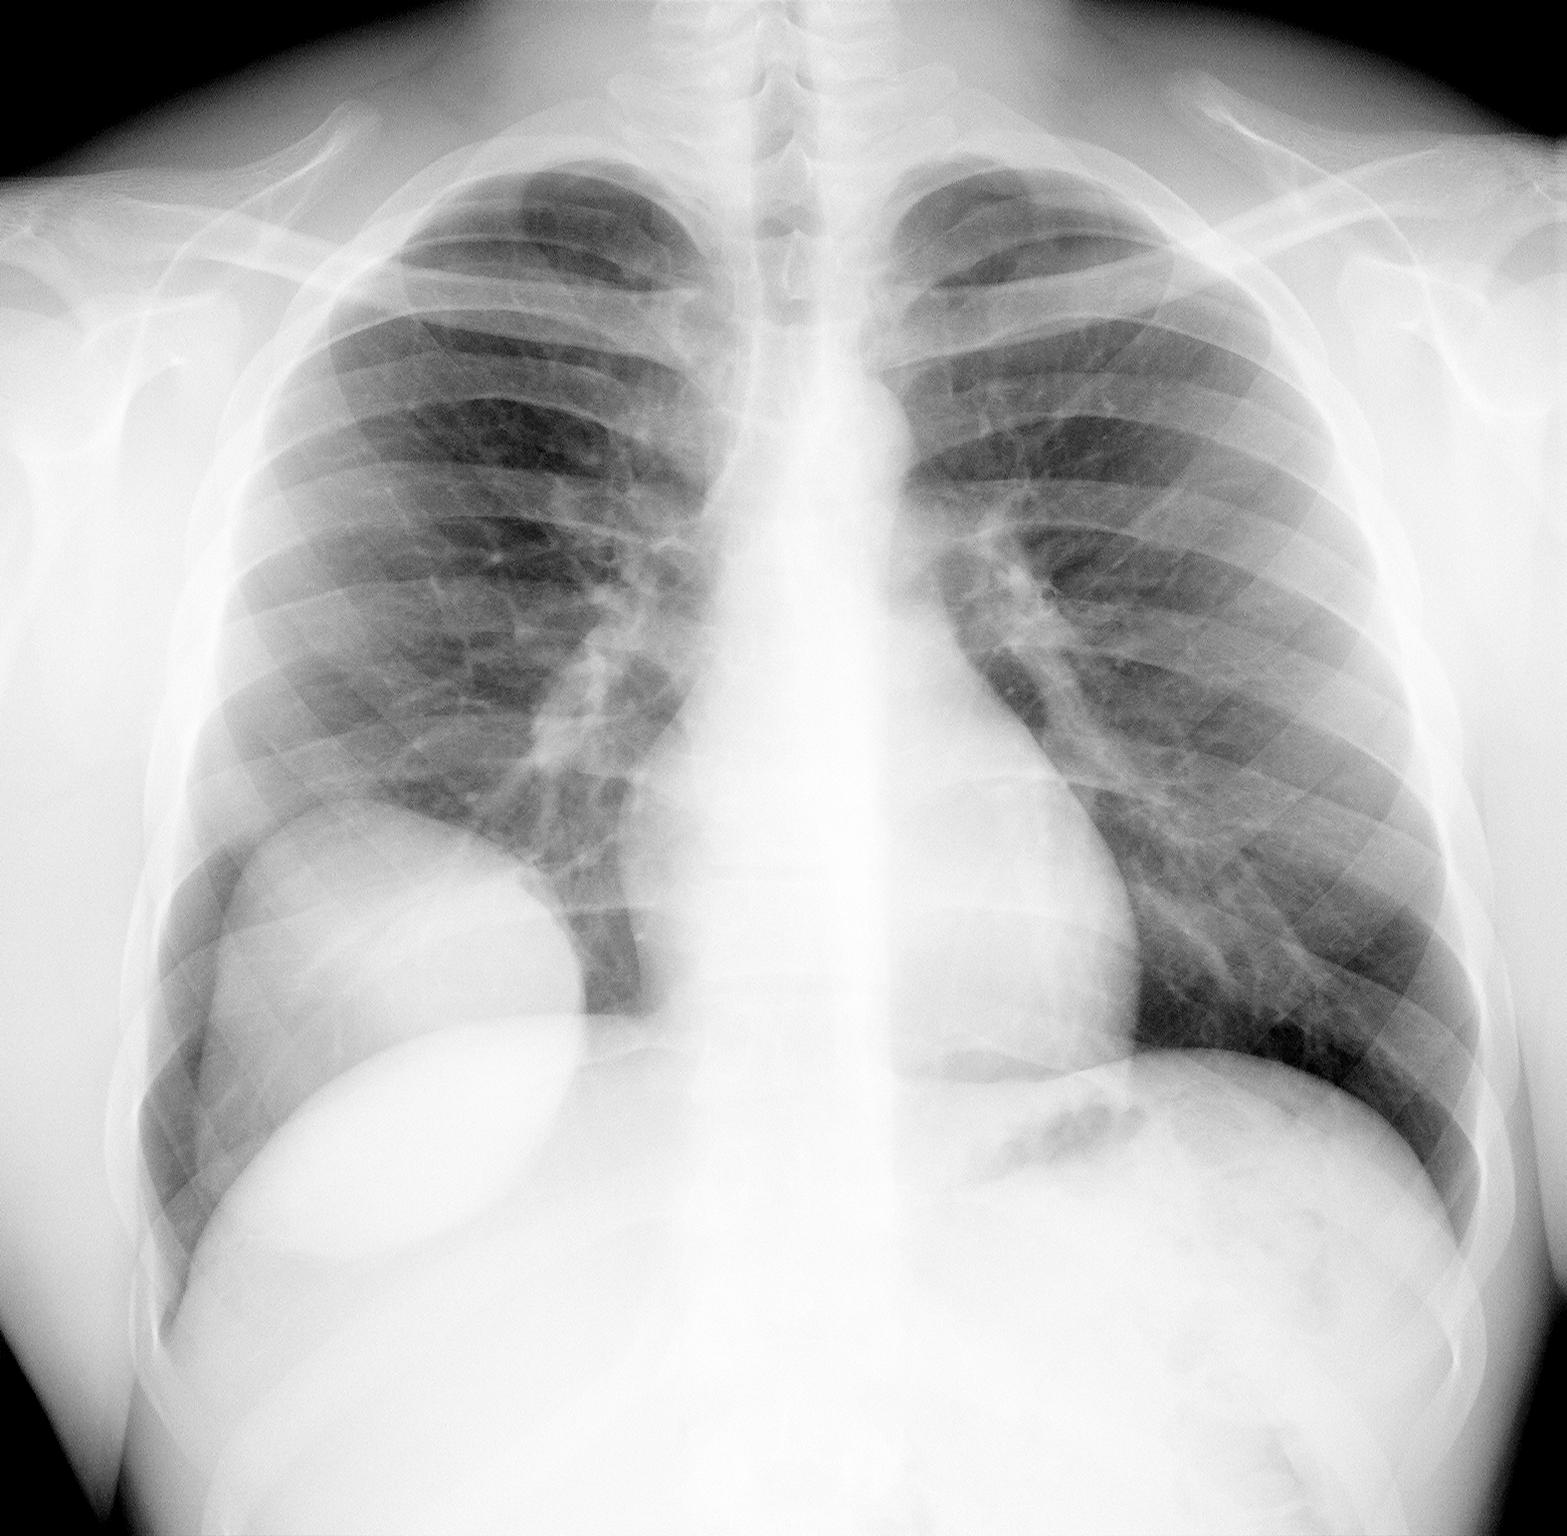

А вот еще скрининговая флг.

Очередной мигрант.  анамнез неизвестен. Как-то великовато для паразитарной кисты.

Почему Вы думаете, что, например, эхинококк не может быть такого размера? Вполне может быть, а судя по боковому там и дочерние кисты не исключаются ))))

Находил как то 14 см в диаметре.

ПОдтверждено При торакотомии.